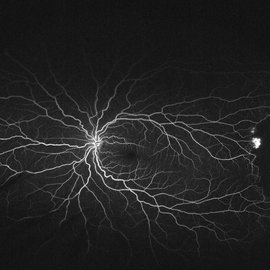

Sickle cell retinopathy (Proliferative) (2 files)

Sickle cell retinopathy (Proliferative) (2 files)

Proliferative sickle retinopathy (1 file)

Proliferative sickle retinopathy (1 file)

Proliferative Sickle Cell Retinopathy (Stage3) (10 files)

Proliferative Sickle Cell Retinopathy (Stage3) (10 files)

Sickle Cell Retinopathy (11 files)

Sickle Cell Retinopathy (11 files)